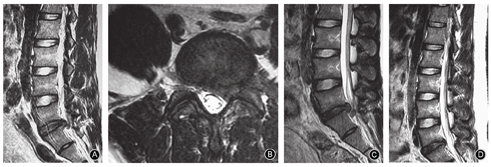

PTED术中经kambin三角(安全三角)穿刺、扩张及安置工作通道时可能损伤出口神经根和背根神经节,尤其椎间孔区域存在神经变异或分支时(图1)[5]。神经根损伤后会出现其支配肌肉的无力和萎缩,相应皮肤支配区感觉减退或缺失,尤其神经断裂会导致其永久性功能缺失,需要功能替代。出口神经根的挤压伤可导致相应支配肌肉无力,如L 4神经根挤压会导致抬腿及伸膝困难,但一般1~3个月内会逐步恢复。PTED术后还可发生神经分布区的感觉减退、异常疼痛,包括痛觉过敏和灼样痛等,并与术前症状不同,这与背根神经节损伤有关,发生率可高达8%~17%。术中反复穿刺、挤压刺激神经根和神经节均为导致其水肿、炎症的原因[3]。Yeung和Tsou[1]回顾性分析1991至1999年PTED治疗的307例腰椎间盘突出症患者,6例(1.9%)术后出现肢体感觉障碍。李长青等[6]报告893例PTED患者中3例发生神经损伤,均为一期行同侧L3,4、L4,5双节段手术者,术后伸膝肌力减弱、跛行,考虑与牵拉和挤压刺激神经有关,予以神经营养、理疗等对症治疗,2例术后3~6个月内完全恢复,1例1.5年仍无明显恢复;24例(2.7%)出现感觉异常,表现为术后神经根性痛觉过敏或灼样痛,经神经营养及理疗1~3周后均恢复。我们的1 300多例PTED患者中发生环锯绞伤出口神经根3例,1例早期硬膜外麻醉过深患者下肢无感觉,1例局部麻醉患者担心影响手术未报告下肢疼痛,1例局麻时操作过快,均为盲视下损伤,结束手术退出工作通道时发现出口神经根断裂,术后均出现足背伸或伸膝无力、肌肉萎缩及相应支配区麻木,半年后功能得到部分代偿。

预防措施包括通过术前MRI了解椎间孔解剖,排除变异神经根,并设计穿刺路径,利用椎间盘突出将硬膜囊和行走神经推向后侧的病理形态,尽量靠近Kambin三角的后内侧即上关节突处置管,避免损伤出口神经根(图2)。此外,还要注意椎间孔外的极外侧突出会把出口神经根向后推挤移位至穿刺入路位置。目前,PTED一般建议采用局部麻醉辅助镇静止痛药物,或采用较浅的麻醉,使患者保持清醒状态,术中刺激神经根会出现疼痛反馈,出现下肢放射痛时要调整扩张和置管的位置或方向。穿刺时尽量向上关节突腹侧穿刺,而不是直接穿刺至椎间盘,缓慢进针也有利于患者反馈、调整位置,正、侧位X线透视监测穿刺针、环锯、工作套管的位置与方向,避免向椎间孔头端或腹侧偏斜,以免损伤出口神经根和神经节。